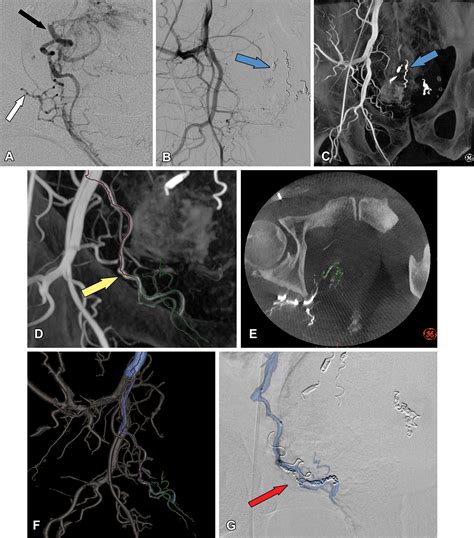

Hemorrhoid Artery Embolization is a cutting-edge, image-guided procedure performed by interventional radiologists. Unlike traditional surgery, which physically removes the hemorrhoidal tissue, HAE works by targeting the blood supply that feeds the hemorrhoids. By reducing the arterial blood flow to the hemorrhoidal plexus, the procedure causes the hemorrhoids to shrink over time, effectively alleviating symptoms like bleeding, pain, and protrusion.

Because it is a minimally invasive technique, it does not require general anesthesia or incisions in the sensitive anal region. Instead, a tiny catheter is guided through a blood vessel in the wrist or groin to the specific arteries supplying the hemorrhoids. Small particles are then injected to block these vessels, successfully reducing the pressure and engorgement of the hemorrhoidal tissues.

2. Guidance: Using real-time X-ray imaging (fluoroscopy), the radiologist navigates a microcatheter through the vascular system.

3. Embolization: Once the specific hemorrhoidal arteries are identified, specialized embolic agents are injected to reduce the blood supply.